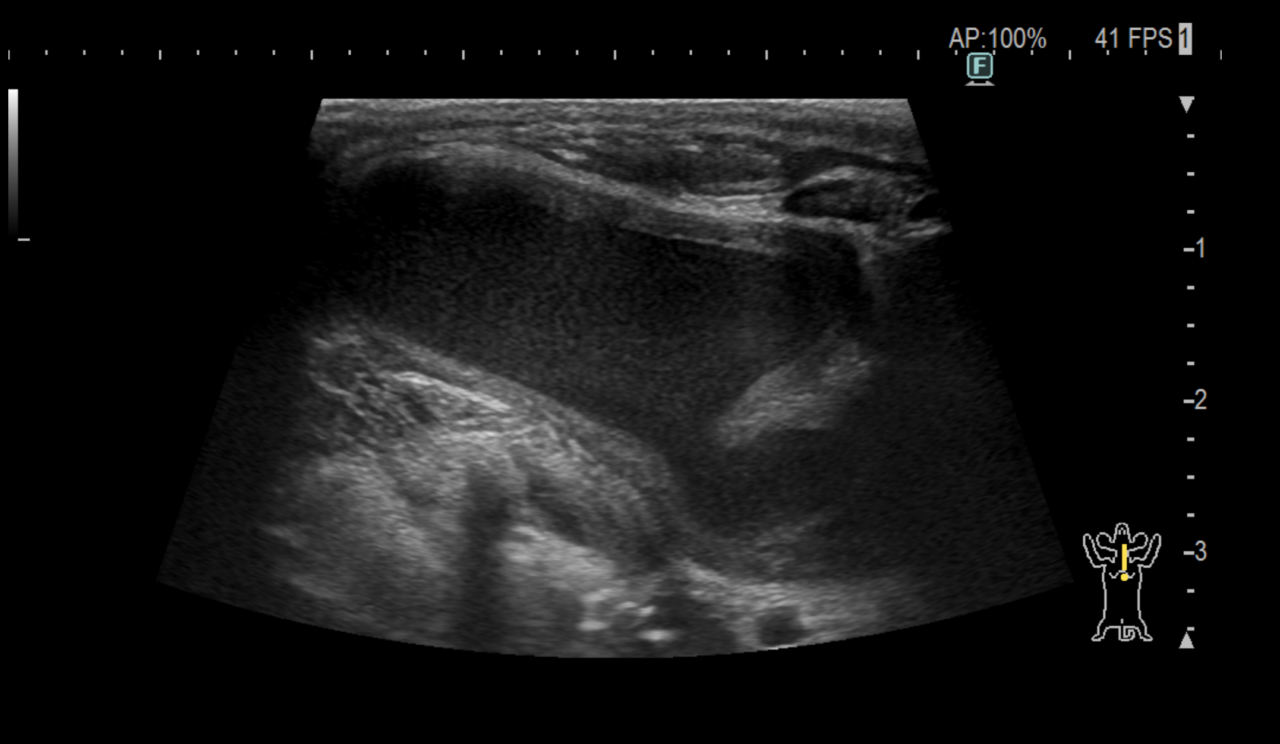

唾液腺嚢胞

高齢犬の頸部に腫瘤ができており、内部に唾液が溜まっているとのことで紹介がありました。

下顎には唾液腺が存在し、ここで作られた唾液が口の中へ分泌されます。唾液腺や、作られた唾液を運ぶ唾液腺管で損傷があると唾液が周囲に漏れて嚢胞を形成します。

根本的な治療として唾液腺ごと切除する方法があります。

この患者さんは切除後は再発もなく良好に経過しています。